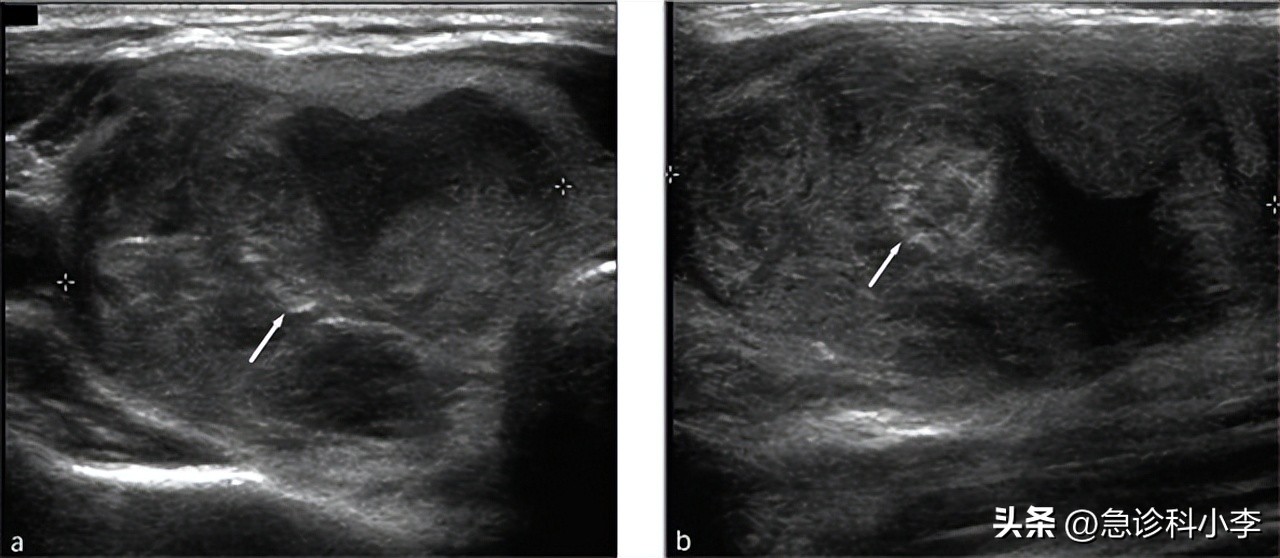

(2)甲状腺B超检查

B超检查下甲状腺一般可显示病变类型,但很难鉴别结节是否为恶性,还需要进一步的检查加以核实。所以B超的检查只能初步判断一下甲状腺的性质,并不能确诊,所以临床一般较少用于甲状腺结节良恶性的判断。